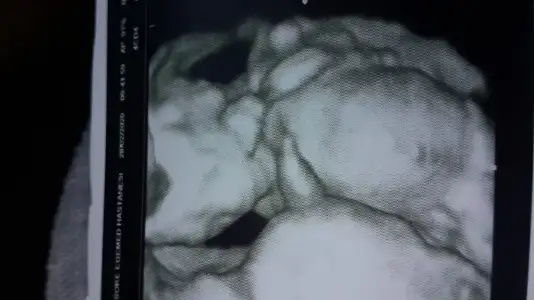

Erkek gibi ama emin olamadım usg net değil başka varsa usg paylaşınSevgili arkadaşlar bize de bakabilir misiniz?12 haftaligiz.Bir kızım var 5 yaşında.İkinci olacakEki Görüntüle 2597265

merhaba biz hala burdayizNet olmamakla birlikte kız gibi başka usg varsa paylaşın yada 12+ usg paylaşın

merhaba biz hala burdayizve kesin olarak cinsiyet öğrenemedik son resmimiz bir tahmin yapılabilinirmi

Net değil usg puslanıyor yakınlaşınca sanki emin degilim kız gibi varsa usg paylaşınIkra meyra Merhabaa 10 haftalik usg ye kiz demistin simdi 12. haftadayiz doktor goremedim dedi tekrar bakar misin :)

Bugün 15+6 olduk sevgiliNubu görünmüyor diger usgden emin değilim yazmıştım başka usg varsa paylaşınkaç haftalık usg

Maalesef elimde bunlardan başka usg yok yorumlarınız için teşekkür ederim son kez bakabilir misiniz rica etsem?kız olursada tabiiki sağlıklı hayırlı evlat olsun çok seviniriz.Ama insan illa ki değişik olsun istiyor

3 usg kaç haftalık nubu dik görünüyor ne bilim cnm dr daha detaylı bakıyor hatta çizeyimMaalesef elimde bunlardan başka usg yok yorumlarınız için teşekkür ederim son kez bakabilir misiniz rica etsem?kız olursada tabiiki sağlıklı hayırlı evlat olsun çok seviniriz.Ama insan illa ki değişik olsun istiyorIkra meyra